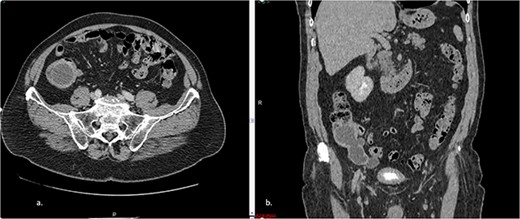

The patient underwent an elective surgical procedure. During the operation, a cystic mass measuring 9.2 × 3.4 × 3.0 cm was found in the right iliac fossa (Fig. 2). The surgical team released Told’s line and the proximal transverse and ascending colon until reaching the terminal ileum and resected the mass with a safety margin. An ileocolectomy with a primary anastomosis was performed using a 75-mm linear stapler reinforced with a continuous suture for hemostasis. This surgical intervention effectively addressed the cystic mass in the patient’s abdomen.

The intraoperative revealed a cystic mass measuring 9.2 × 3.4 × 3.0 cm was found in the right iliac fossa.